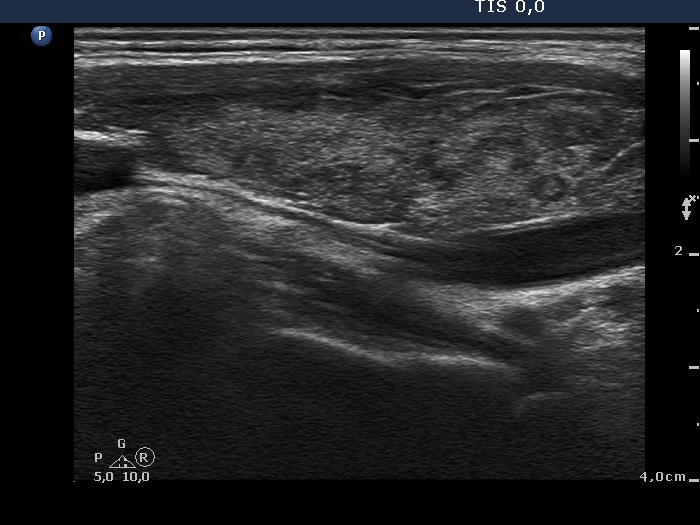

First examination (first row of images):

Clinical presentation. A 26-year-old woman requested an evaluation because of complaints suggesting hyperthyroidism. She lost 3 kg in weight, had fatigue and nervousness. She had been treated for Graves' disease for one year, the thyrostatic was stopped 10 months ago.

Palpation: no abnormality.

Laboratory examination: TSH 0.91 mIU/L, FT4 13.4 pM/L.

Ultrasonography. The thyroid was echonormal and presented several hypoechogenic areas. The echogenicity index was < 10%. The vascularization was average or a bit decreased.

Suggestion: to continue follow-up, hormonal evaluation in a year, in the event of complaints suggesting relapse of hyperthyroidism or pregnancy at once. We advised to visit a gastroenterologist.